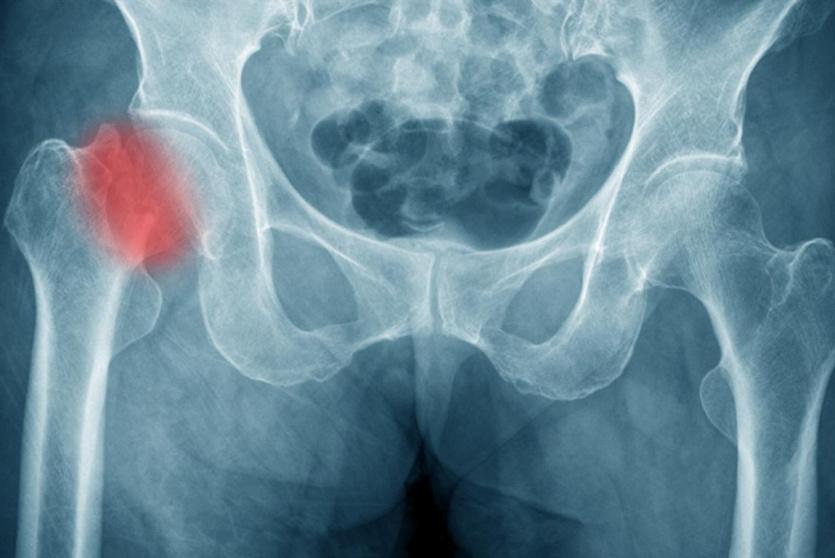

دراسة: النساء النباتيات أكثر عرضة لكسور الورك

وجدت دراسة جديدة أن النساء اللواتي يتبعن نظاما غذائيا نباتيا يرتفع خطر الإصابة لديهن بكسر الورك بنسبة 33% مقارنة بمن يأكلن اللحوم.

ولاحظ الباحثون بعد حوالي 20 عاما ،822 كسرا في الورك بين النساء، حوالي 3%، وأن ارتفاع خطر الإصابة بكسر الورك كان فقط بين النباتيات مقارنة بالنساء اللواتي تناولن اللحوم بانتظام.